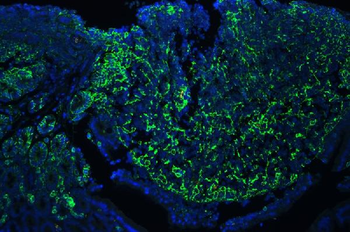

10 μg, 100 μg - Anti-S100 alpha 6/S100A6 Antibody [orb315184]

FC, ICC, IF, IHC, WB

Human, Mouse, Rat

Rabbit

Polyclonal

Unconjugated

10 μg, 100 μg - Anti-HSD11B2 Antibody [orb316541]